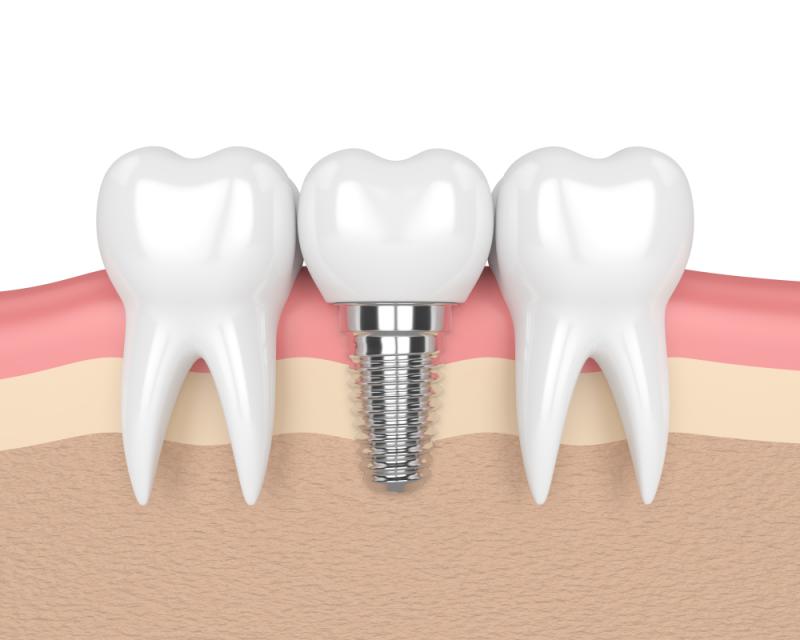

Wstawianie implantów zębów, innymi słowy, chirurgia implantów dentystycznych, to zabieg polegający na zastąpieniu korzeni zębów specjalnymi, metalowymi, śrubopodobnymi wkładami oraz zastąpieniu uszkodzonych lub brakujących zębów sztucznymi zębami, które wyglądają zupełnie jak prawdziwe. Nie jest to zabieg wyłącznie estetyczny, bowiem chirurgia implantów dentystycznych może stanowić alternatywę dla protez lub mostów, które nie pasują do siebie. Jest też jedną z opcji, gdy z powodów zdrowotnych nie jest możliwe zbudowanie protezy lub uzupełnienia mostów.

Implanty powstają z czystego tytanu, są dość małe i mieszczą się w kości pod dziąsłem, zachowując się jak zwykłe korzenie zębów. Istnieją trzy popularne typy implantów dentystycznych, które można zastosować: wewnątrzkostny (śródkostny; najbardziej popularny, wymaga zdrowej szczęki), podokostnowy (stosowany, gdy pacjent nie ma wystarczającej ilości kości szczęki) i jarzmowy (najbardziej skomplikowany implant).

Implanty dentystyczne są umieszczane chirurgicznie w kości szczęki, gdzie służą jako korzenie zębów, których brakuje. Charakterystyczne dla tego zabiegu jest to, że tytan znajdujący w implantach stapia się po jakimś czasie z kością szczęki, implanty dzięki temu nie ślizgają się, nie hałasują i nie powodują uszkodzeń kości, tak jak może się to stać w przypadku stałych mostów lub protez. Implanty zatem będą odpowiednie dla osób, które mają jeden lub więcej brakujących zębów, prawidłowe kości szczęki lub możliwość wykonania przeszczepu kości w szczęce, zdrowe tkanki jamy ustnej, brak problemów z gojeniem, Implanty są także wskazane dla osób, które nie chcą lub nie mogą nosić protez, które chcą poprawić artykulację oraz są gotowi poświęcić czas na ten proces (w sumie trwa to parę miesięcy). Ponadto warto rozważyć zabieg, jeśli ząb nie może być uratowany w inny sposób. Czasami stosuje się implanty tylko ze względów estetycznych, np. jeśli w jamie ustnej między zębami są znaczące przerwy albo gdy szczęka ucierpiała w wyniku urazu, choć np. w przypadku wyszczerbienia, można zastosować mniej inwazyjne metody, np. wiązanie kompozytowe.